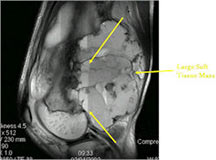

- The cystic spaces filled with hemorrhagic material leads to the presence of fluid-fluid levels on MRIs (so called ABC-like changes or telangiectatic change)

MRI/CT:

- Fluid-fluid levels secondary to cystic cavities filled with blood products. The sediment from blood products settle to the gravity dependent area of the cavity and the fluid component floats to top thus forming a fluid-fluid level.

- MRI and CT are also useful for demonstrating the local extent of the tumor and any soft tissue mass